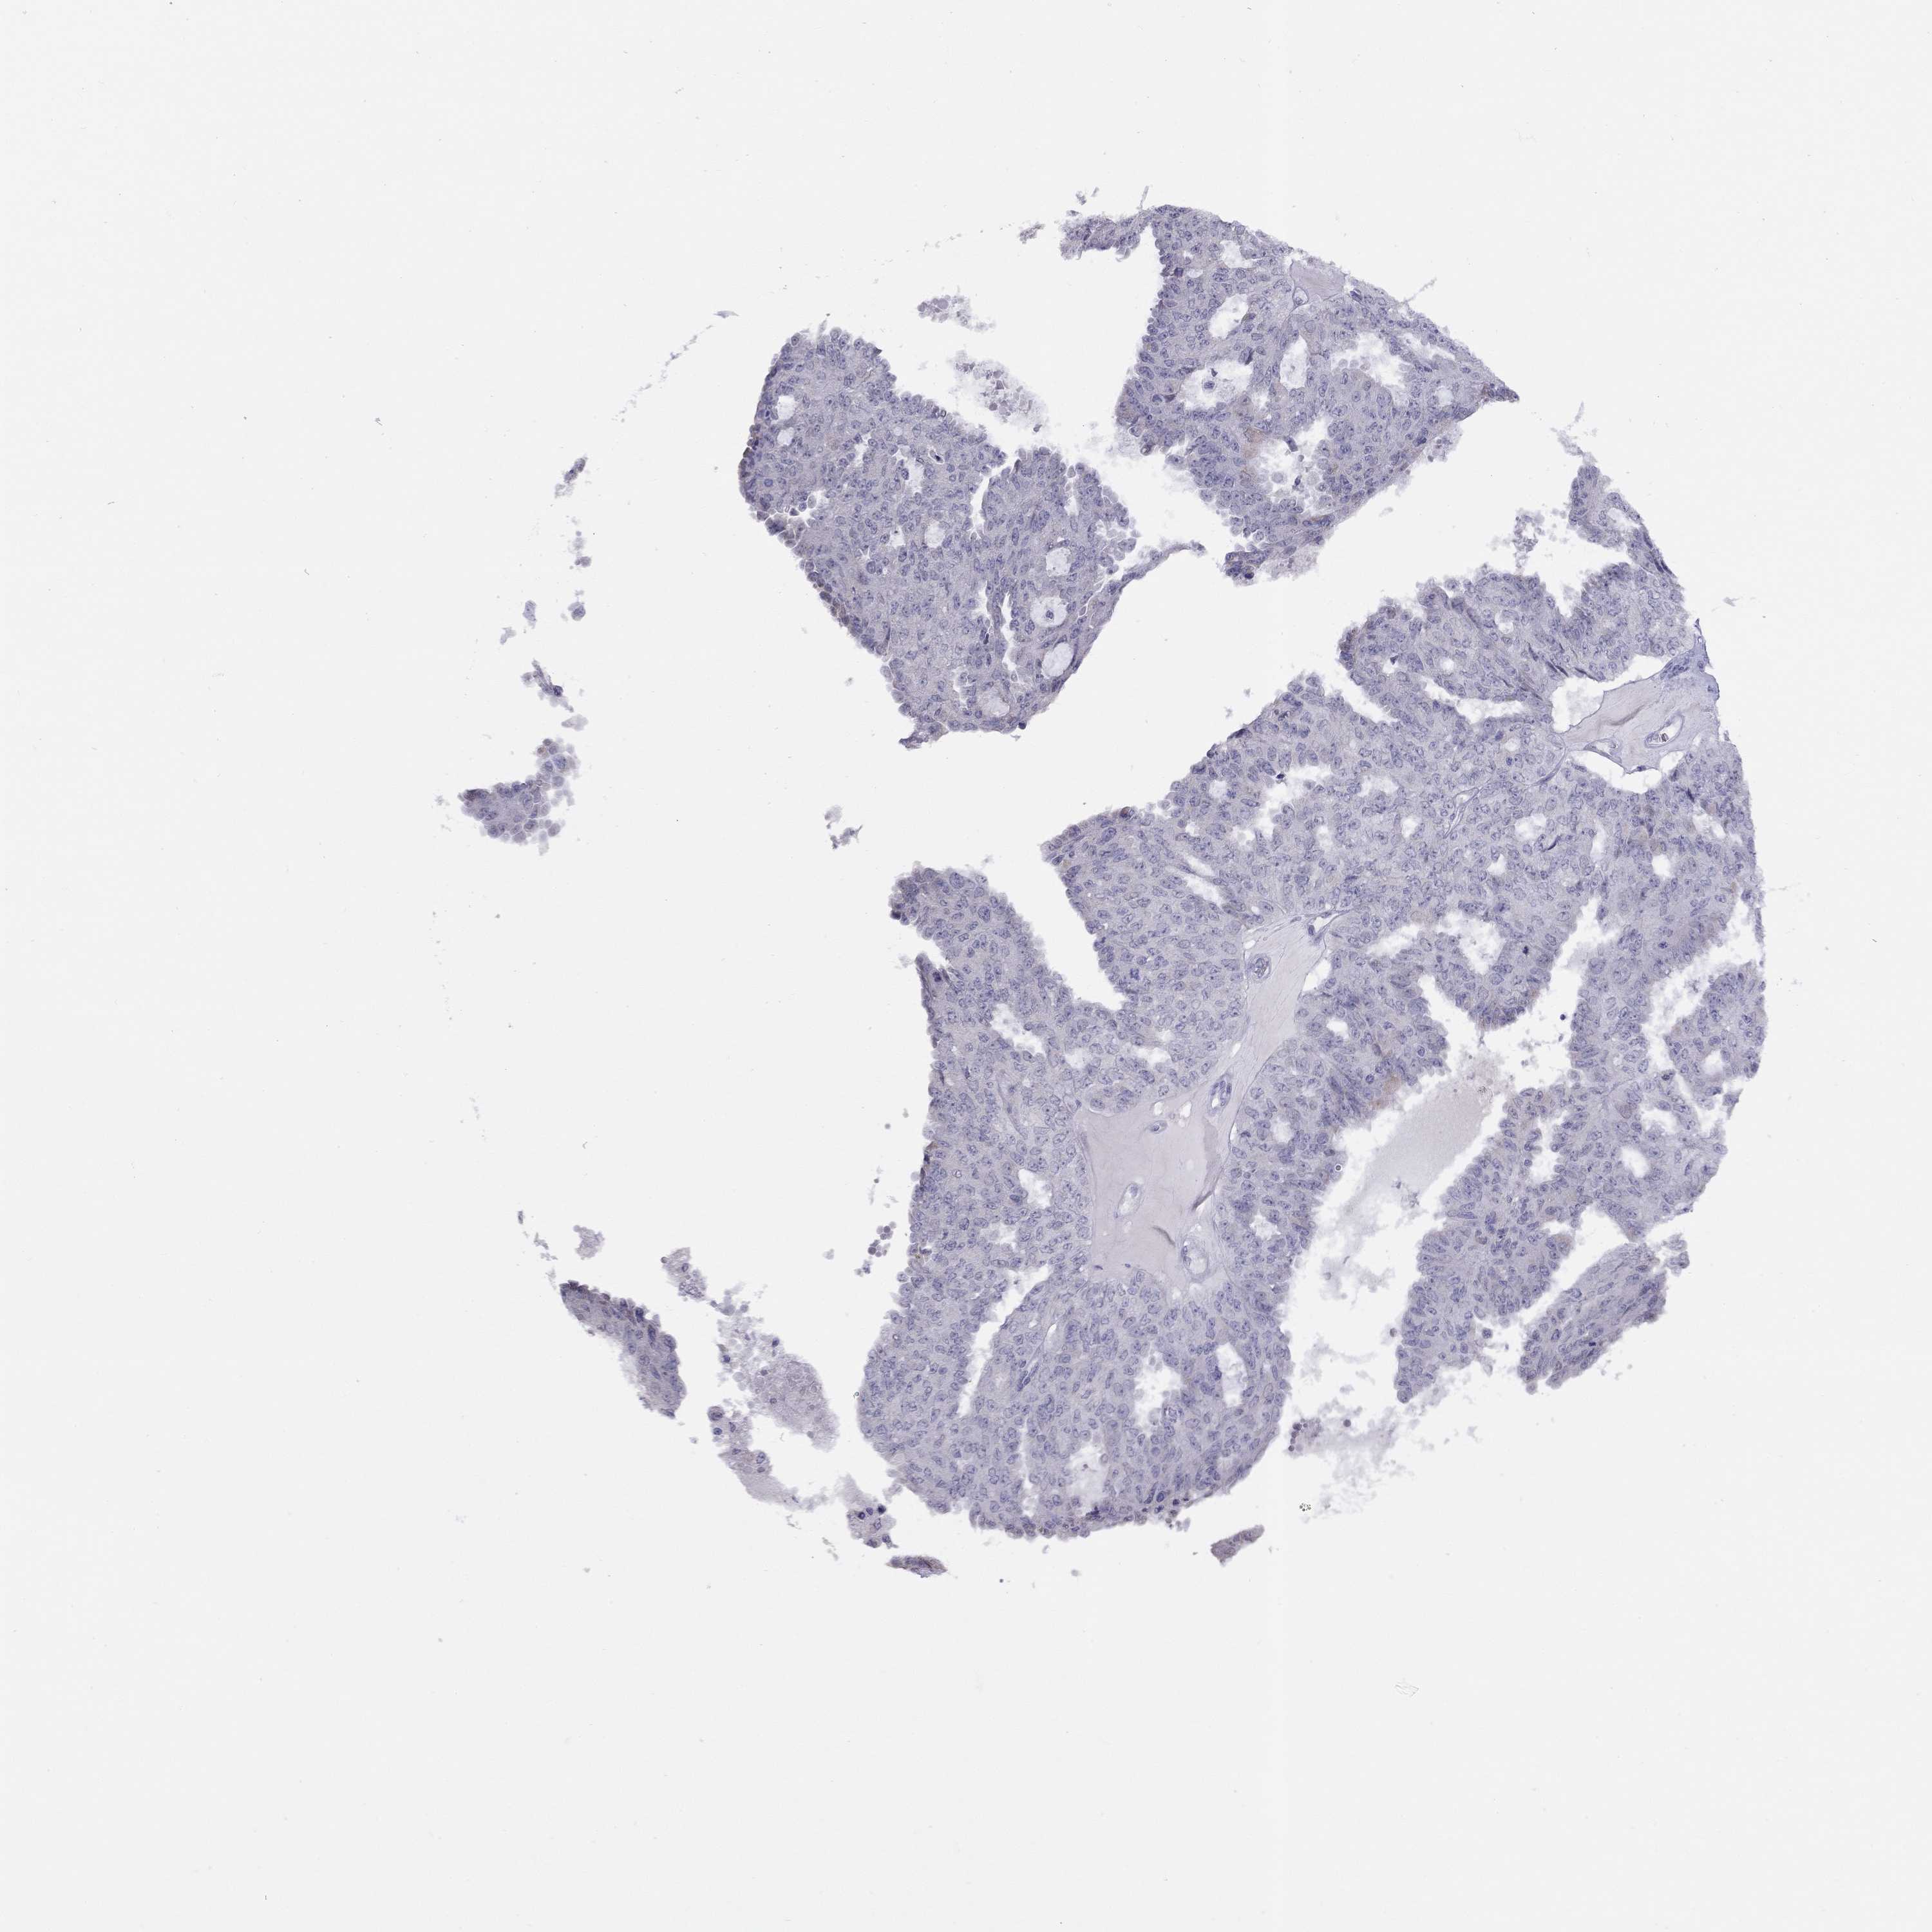

OVARIAN CANCER - Protein expressioni

A mouse-over function shows sample information and annotation data. Click on an image to view it in a full screen mode. Samples can be filtered based on level of antibody staining by selecting one or several of the following categories: high, medium, low and not detected. The assay and annotation is described here.

Note that samples used for immunohistochemistry by the Human Protein Atlas do not correspond to samples in the TCGA dataset.

Antibody stainingi

Antibody staining in the annotated cell types in the current human tissue is reported as not detected, low, medium, or high, based on conventional immunohistochemistry profiling in selected tissues. This score is based on the combination of the staining intensity and fraction of stained cells.

Each image is clickable and will lead to virtual microscopy that enables deeper exploration of all samples and also displays staining intensity scores, fraction scores and subcellular localization as well as patient and tissue information for each sample.

Antibody HPA076164

Staining

High

Medium

Low

Not detected

Intensity

Strong

Moderate

Weak

Negative

Quantity

>75%

75%-25%

<25%

None

Location

Nuclear

Cytoplasmic/membranous

Cytoplasmic/membranous,nuclear

Cystadenocarcinoma, mucinous, NOS